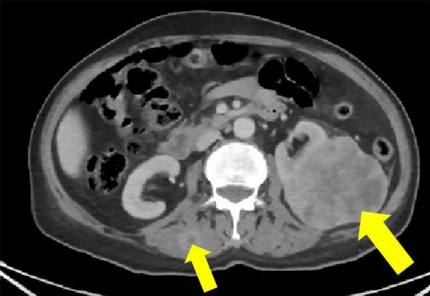

However, there was a progressive nodule in the left perinephric fat, inseparable from the perinephric fascia, 1.6x1.3 cm (compared to 0.5 cm previously). There was also a progression of the right iliac bone lesion, which was 5.7x4x7.6 cm but is now 6.4x5.1x8.7 cm. It was infiltrating the right iliac bone and the right psoas muscle.

So, despite the stability of the disease, there was a progression of the right iliac bone and a new lesion in the left perinephric fat. This was odd for lung cancer. So, we took a biopsy from the single progressive left perinephric lesion.

Fig.7: Left perinephric fat lesion.

Fig.8: Core biopsy from the left perinephric fat lesion.

Fig 11: CT abdomen